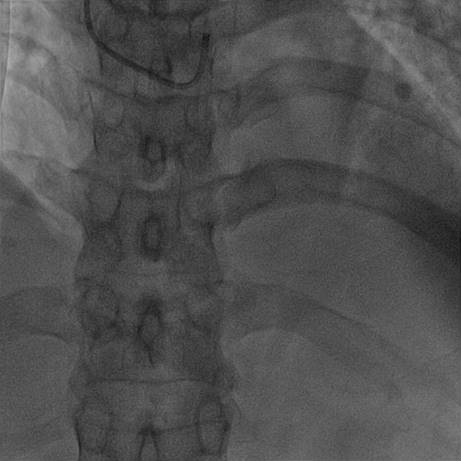

【冠脉造影】

造影结果(一)

前降支中段闭塞

造影结果(二)

球囊扩张

造影结果(三)

前降支中段闭塞血管显影

【造影结论及应对策略】

本病例行冠脉造影发现:前降支中段闭塞,前降支近端粥样硬化伴局部Ⅳ度狭窄,右冠状动脉中段、回旋支粥样硬化,造影后向患者家属交代病情,与家属沟通后决定做介入治疗。

【手术过程】

患者因急性前壁心肌梗死在DSA下行急诊PCI术,常规消毒右手前壁、右腹股沟区,铺洞巾,穿刺右侧桡动脉并置6F桡动脉血管鞘,注入肝素2000U、硝酸甘油100ug、利多卡因40mg后分别以JL3.5、JR4造影管造影取像,不同角度造影显示:LM未见明显异常病变,LAD-近端85%弥漫性病变,中段以远total病变,LCX、RCA未见异常狭窄病变。

结合患者病史考虑罪犯血管为LAD,需行PCI治疗,追加肝素7000U,经桡动脉置入EBU3.5大腔至LCA开口,送入runthrough导丝不能通过闭塞病变,更换P50导丝反复尝试通过闭塞端至LAD远端,以2.0*15mm球囊12atm预处病变10秒2次,于闭塞病变处植入2.75*24mm EXCEL支架,及近段植入3.0*24mm EXCEL支架各一枚,撤出球囊和导丝后复查造影,无残余狭窄。

【手术总结】

术前后病变部位造影图